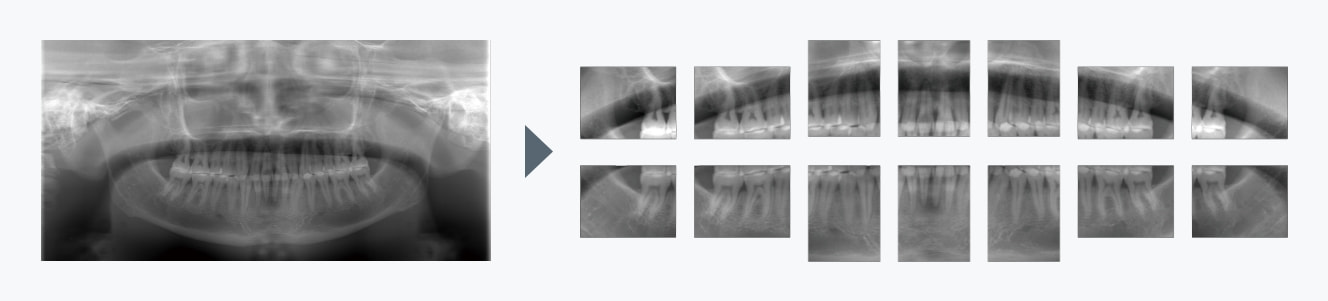

デンタル画像への切り出し

パノラマ画像からそのままデンタル画像(10枚法、14枚法)への切り出しが可能です。

14枚法によるデンタル撮影テンプレート例

※1回の撮影において複数の診療区分を併せて算出することはできません。